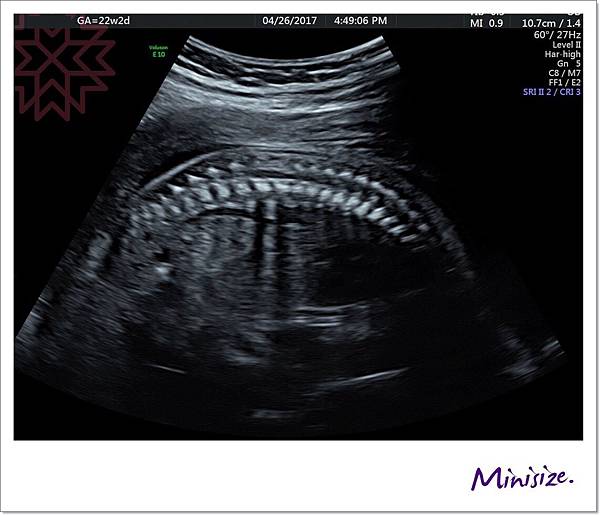

脊椎

骨骼要呈現排列整齊相互對稱

背部皮膚的表層也要光滑 完整連接